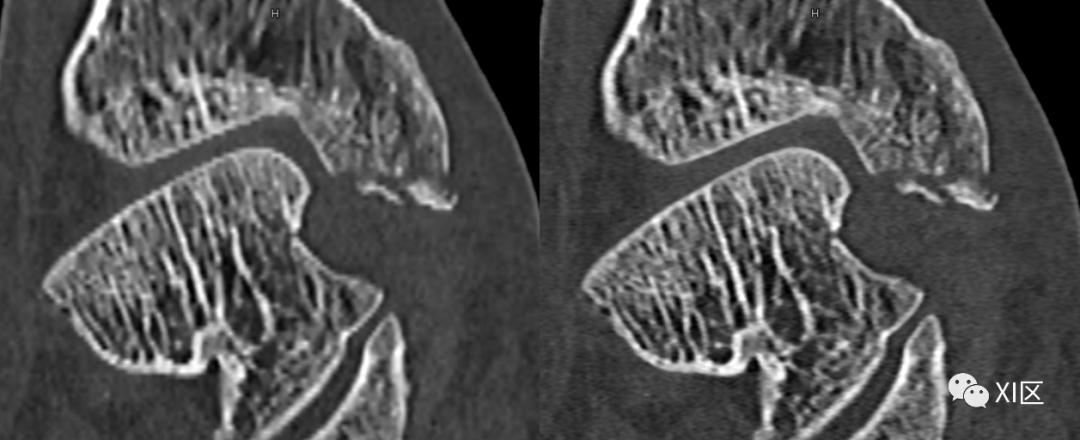

SOMATOM Definition Flash光子CT常规重建0.6 mm(128x0.6 mm)图像(左)与IVR重建0.6 mm(384x0.6 mm)图像(右)比较。使用IVR技术的图像关节面更平滑,骨小梁及骨折细节显示更清晰。

SOMATOM Force CT常规重建0.6 mm(192x0.6 mm)图像(左)与IVR重建0.6 mm(288x0.6 mm)图像(中)0.6 mm(576x0.6 mm)比较(上排:全局视图;下排:局部放大显示)。使用IVR技术的图像关节面更平滑,骨小梁及骨折细节显示更清晰。